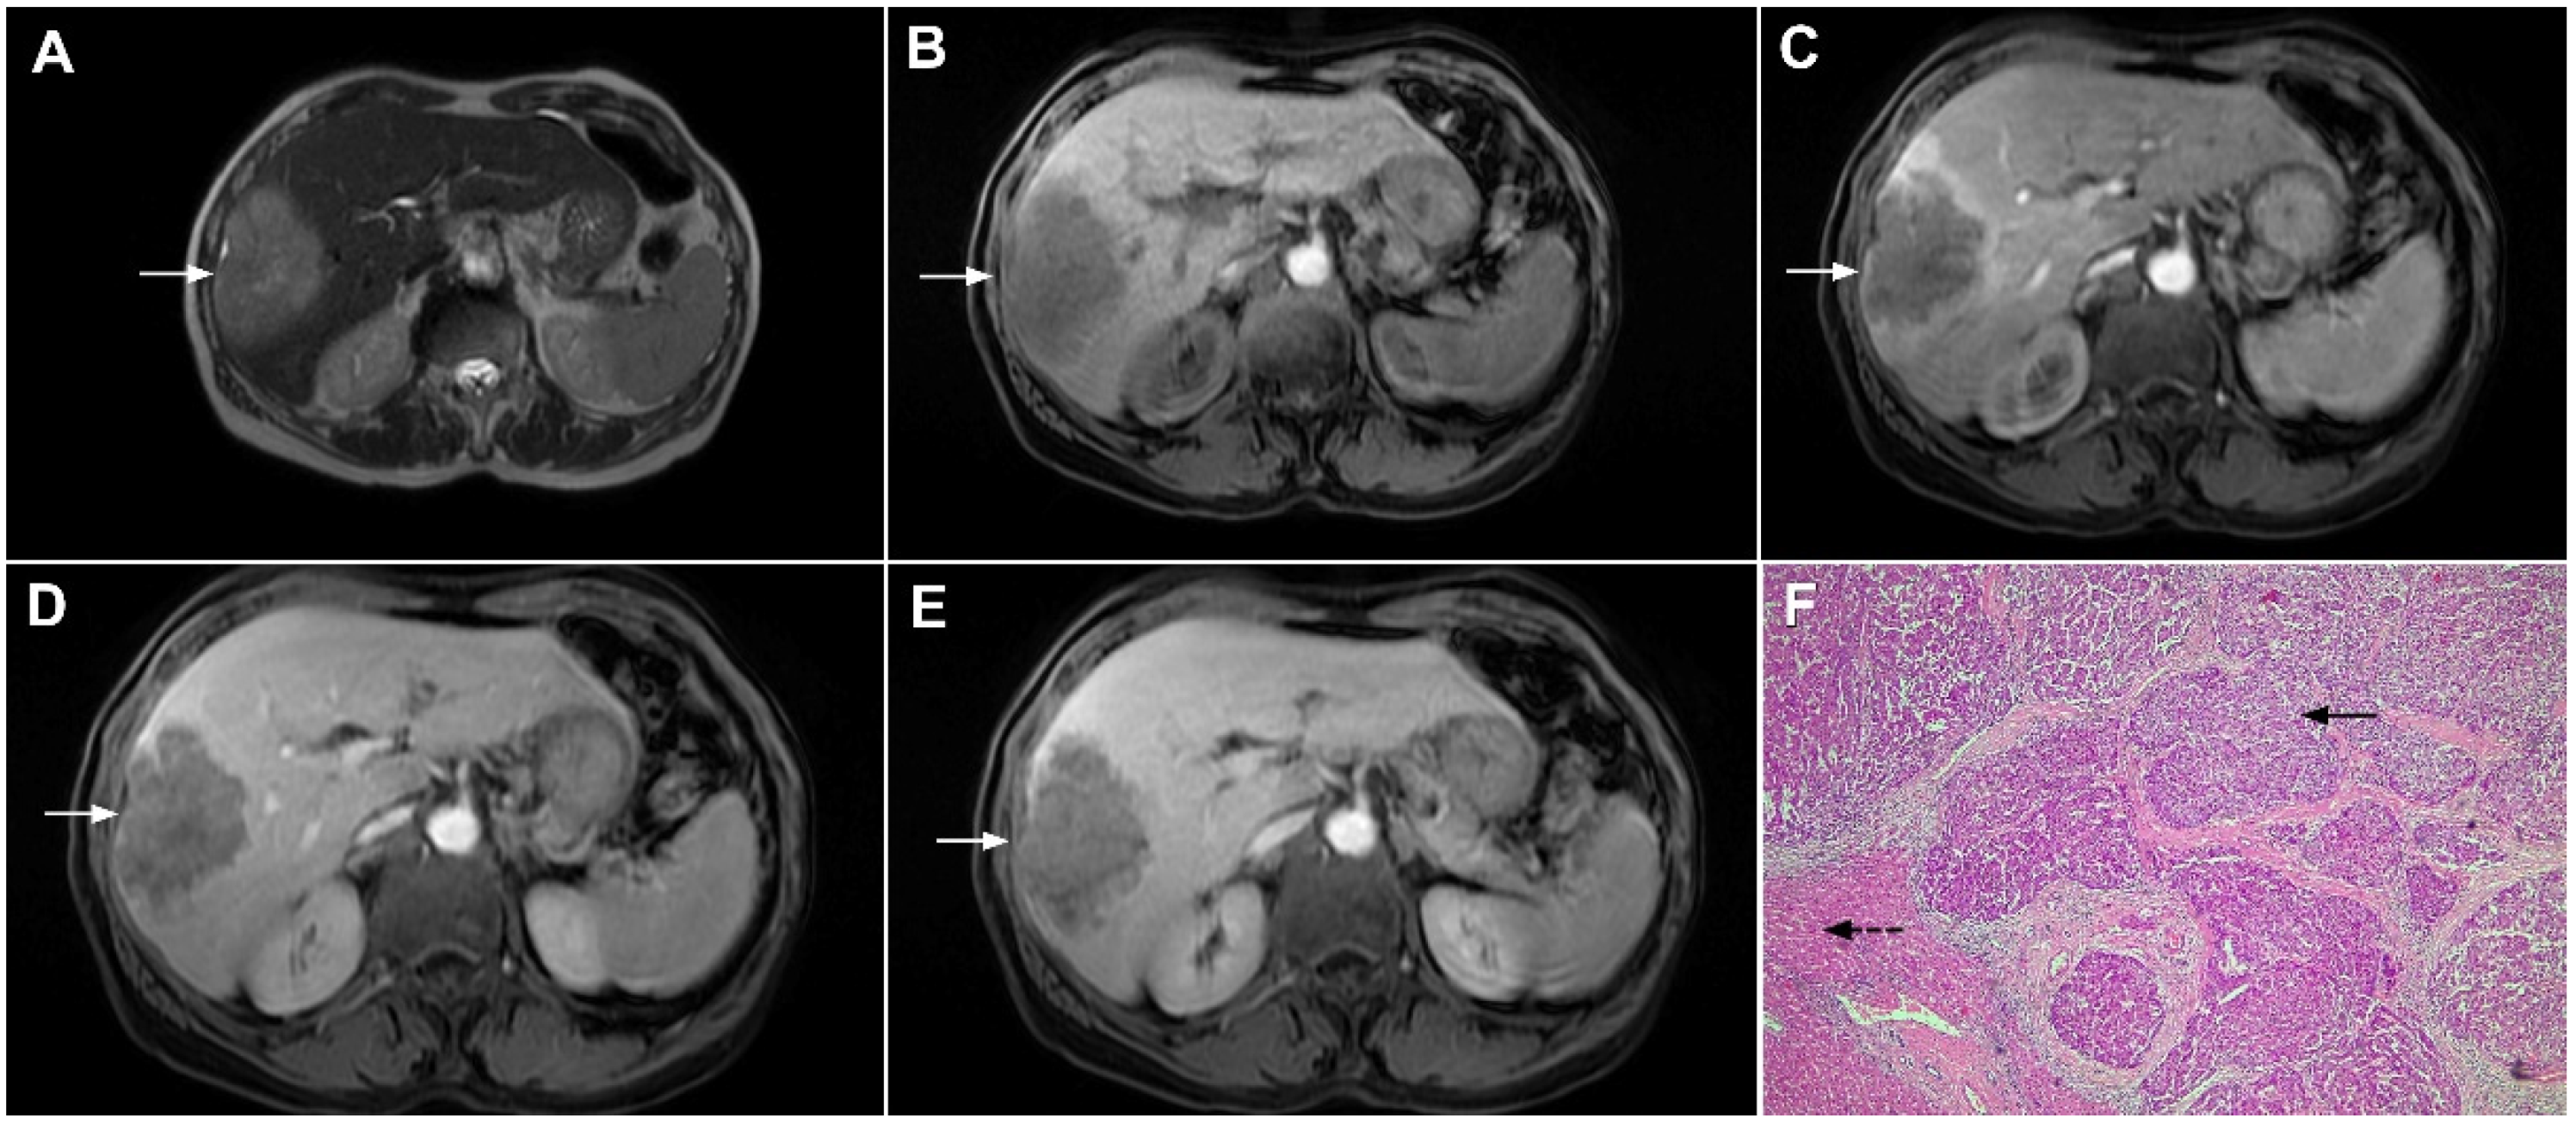

3.1.2. Sclerosing Hemangioma

- Doyle, D.J.; Khalili, K.; Guindi, M.; Atri, M. Imaging features of sclerosed hemangioma. AJR Am. J. Roentgenol. 2007, 189, 67–72. [Google Scholar] [CrossRef]

- Song, J.S.; Kim, Y.N.; Moon, W.S. A sclerosing hemangioma of the liver. Clin. Mol. Hepatol. 2013, 19, 426–430. [Google Scholar] [CrossRef]

- Ridge, C.A.; Shia, J.; Gerst, S.R.; Do, R.K. Sclerosed hemangioma of the liver: Concordance of MRI features with histologic characteristics. J. Magn. Reson. Imaging 2014, 39, 812–818. [Google Scholar] [CrossRef] [PubMed]

- Shin, Y.M. Sclerosing hemangioma in the liver. Korean J. Hepatol. 2011, 17, 242–246. [Google Scholar] [CrossRef] [PubMed]

- Andeen, N.K.; Bhargava, P.; Park, J.O.; Moshiri, M.; Westerhoff, M. Cavernous hemangioma with extensive sclerosis masquerading as intrahepatic cholangiocarcinoma—A pathologist’s perspective. Radiol. Case Rep. 2015, 9, 937. [Google Scholar] [CrossRef] [PubMed][Green Version]

- Renzulli, M.; Capozzi, N.; Clemente, A.; Tovoli, F.; Cappabianca, S.; Golfieri, R. What happened to my liver lesion (Hepatic Sclerosed Hemangioma)? Let’s not forget (radiological) history. Acta Gastroenterol. Belg. 2019, 82, 554–555. [Google Scholar] [PubMed]